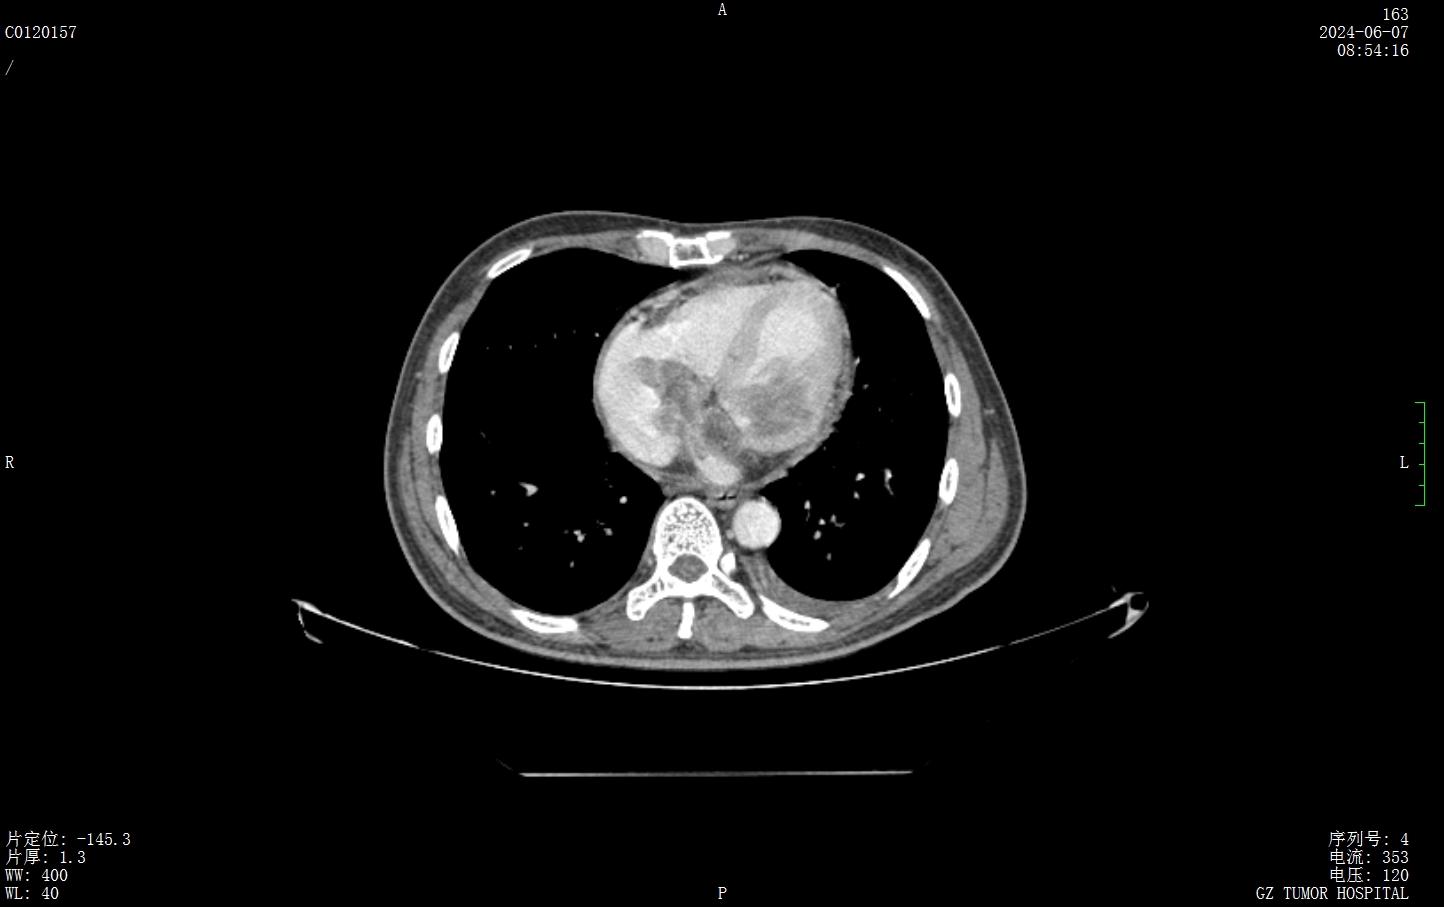

今年5月,阿涛又开始出现明显的不适感,胸闷、气促,心率快导致他只能卧床,无法自主行动。经过心脏超声检查发现,阿涛的左心室和右心房内竟然分别有一个3.1×2.9厘米和3.5×4.1厘米的肿瘤。

由于发现阿涛的心脏里含有大量心包积液,专家团队紧急为他进行了心包穿刺术。第一天医生就引流出了300ml血性心包积液,第二天又是300ml。李卫东称,阿涛的心肌被肿瘤广泛浸润,如果不采取有效控制,病情将无法逆转。如果心包积液持续压迫心脏会导致心脏的停搏,生命岌岌可危,同时治疗难度也非常大。

由内科、放疗科、外科、ICU、医学影像科专家组成的团队,在有限的病例报道中连夜进行讨论分析、勾画靶区、制订放疗计划,做好充分的应急方案。最终,团队决定采用螺旋断层放射治疗系统(TOMO)设备,为阿涛进行精准放疗。

广医肿瘤放疗科放疗中心主任张书旭介绍,TOMO以螺旋CT旋转扫描方式,在CT引导下360度聚焦断层照射肿瘤,能对恶性肿瘤患者进行高效、精确、安全的治疗。TOMO能够按照治疗计划精准定位,对肿瘤部位设置千万条射线束,而对其他的健康组织避免高剂量照射,充分保护正常心肌以及周边器官的功能,精准度能达到0.1毫米。

历时约6周,阿涛全程接受了28次心脏肿瘤放疗。放疗5次后,阿涛便能开始独立行走和进食,放疗9次后已经没有了心包积液,心包穿刺引流管得以拔除。刘锦全表示,由于心包积液的变化会导致肿瘤位置变化,放疗期间医生们调整了3次放疗计划,在保障有效放疗剂量的同时,尽可能保护心脏功能。